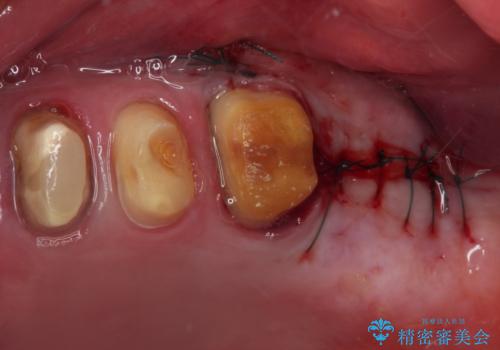

上顎前歯に歯周ポケットの深い部分がありましたが、インプラントの仮歯で奥歯がしっかりと噛めるようになると、1年程度で深い歯周ポケットは解消されました。

前歯部の審美面も大幅に改善され、大変満足していただけました。